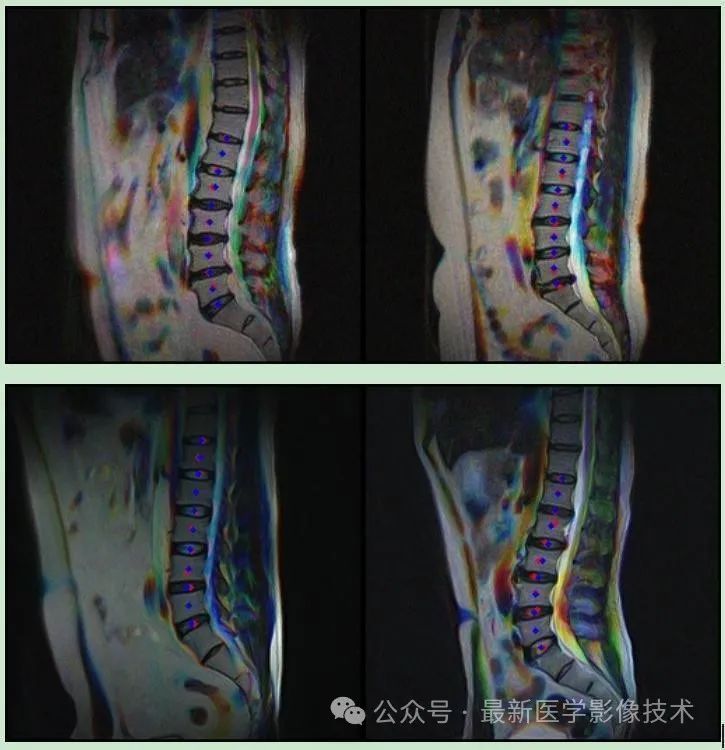

1.1、由于标注数据里有studyUid,seriesUid,instanceUid这三个tag信息,所以解析标注数据并根据这三个tag信息从图像数据中找到相匹配的序列图像,此外标注的关键点坐标是再序列图像中的中间位置进行标注的,而中间帧相邻图像的关键点的位置和特性是非常相似的,选取中间帧相邻的图像,通过通道叠加的方式来增加多样性。效果如下所示。